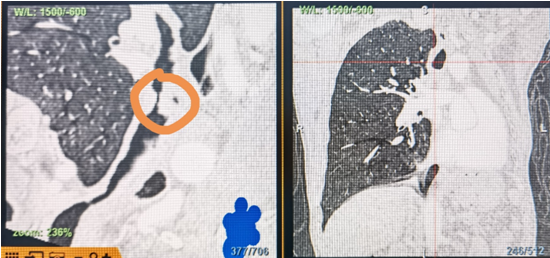

時(shí)間就是生命!了解患者病情后,歐陽海峰立刻啟動(dòng)氣道梗阻緊急救治通道,協(xié)調(diào)院前轉(zhuǎn)運(yùn),急診快速入院流程。凌晨患者入院胸部CT顯示,現(xiàn)存唯一的呼吸通道在右主支氣管處,狹窄處僅約3毫米,患者命懸一線!